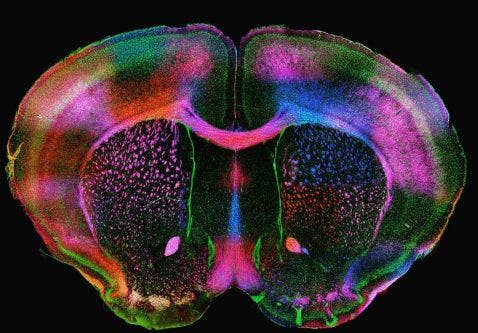

Imagen de microscopio de un cerebro de ratón expresando proteínas de mielina

Todos los cerebros son bellos, pero este "cerebro en arco-iris" es realmente único. Esta bonita imagen de un cerebro de ratón está expresando las proteínas de mielina PLP (proteína proteolípida) y MBP (proteína básica de mielina) en diversos colores. La mielina es una sustancia grasa que rodea los axones de las células nerviosas y actúa como aislamiento. Las proteínas no solo tienen un aspecto bonito, sino que también trabajan para mantener la estructura de la mielina.

Imagen por cortesía de Diara Santiago González. Capturada en una unidad de barrido por disco de Olympus (DSU).